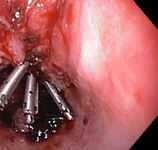

Três clipes tipo "through-the-scope" para o fechamento completo do defeito na mucosa

Do acervo de Juan Carlos Munoz, MD, University of Florida